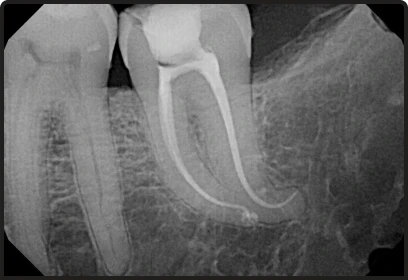

- We utilize digital imaging and rotary endodontics to provide more precise results and faster recovery times.

Root Canal Therapy Re-Treatment

A specialized procedure to fix a previous root canal treatment that has failed.

- Involves removing old filling material and disinfecting complex canal branches.

- Aimed at saving a tooth that would otherwise require extraction.